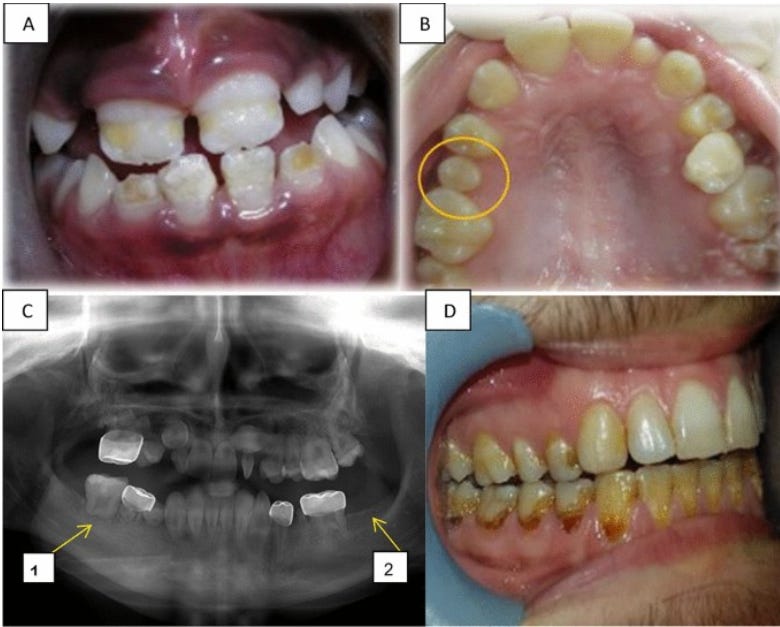

Abnormalities included missing or small teeth, root development and enamel structure damage, over-retention of primary teeth; impaction; premature eruption; decreased temporomandibular joint (TMJ) mobility; inability to open the mouth or jaw, and facial deformities.

Long-term dental effects. (A) Hypoplasia in the front upper and lower teeth of a girl aged 9 years, treated for ALL at age 3.5 years. (B) Microdontia showing the second upper right premolar in a girl of12 years, treated for neuroblastoma at age 4 years. (C) A panoramic radiograph of a 12-year-old boy diagnosed with Burkitt's lymphoma at age 4 years, revealing: C1. Altered root development at the first lower right molar, C2. Hypodontia of the second lower left molar. (D) Radiation caries in a 21-year-old boy treated for a neuroectodermal tumor at the age of 14 years. CREDIT: Elinor Halperson/Hebrew University-Hadassah School of Dental Medicine.